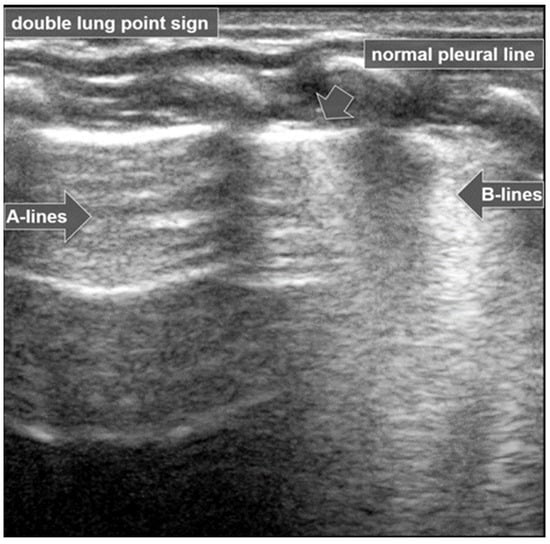

3.1.8. Double-Lung-Point Sign

The “double-lung-point sign” is a sharp sonographic demarcation visible between normally aerated upper lung fields and lower lung zones, with multiple and/or confluent B-lines indicative of interstitial edema (Figure 9).

Double-lung-point sign: Normally aerated upper lung fields (arrow) and lower lung zones with multiple confluent B-lines (open arrow).

This pattern is characteristic of Transient Tachypnoea of the Newborn (TTN) [27,28], where a marked difference in lung echogenicity between superior and inferior regions can be visualized by ultrasound [6,26]. This finding has been reported to have a specificity of up to 100% for TTN [6,17,26], and is not typically present in other neonatal pulmonary conditions such as atelectasis, pneumothorax, pneumonia, or pulmonary hemorrhage [17,29].

In TTN, LUS findings include the double-lung-point sign, pulmonary edema, alveolar–interstitial syndrome, compact B-lines, and a regular pleural line without subpleural consolidation [20,35].

The hallmark LUS finding of TTN is the double-lung-point (Figure 11), a clear demarcation between the inferior lung fields, which appear normally aerated, and the superior fields, which show dense, confluent B-lines consistent with interstitial fluid accumulation. As previously mentioned, the double-lung-point has been reported with a specificity as high as 100% for TTN [6,17,26,36]. Notably, this LUS pattern is not typically observed in other neonatal pulmonary conditions such as pneumonia, pneumothorax, atelectasis, or pulmonary hemorrhage. The presence of these features in LUS, particularly the double-lung point and the absence of subpleural consolidations, reinforces the diagnostic value of point-of-care lung ultrasound in distinguishing TTN from other causes of neonatal respiratory distress [20,29,37,38,39].